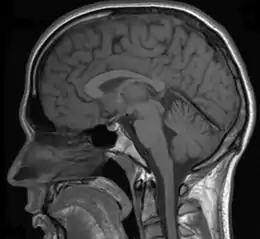

Various studies have used MRIs (magnetic resonance imaging) to measure brain activity when individuals detect (or fail to detect) a change in the environment. When individuals detect a change, the neural networks of the parietal and right dorsolateral prefrontal lobe regions are strongly activated.[32][33] If individuals were instructed to detect changes in faces, the fusiform face area was also significantly activated. In addition, other structures such as the pulvinar, cerebellum, and inferior temporal gyrus also showed an increase in activation when individuals reported a change.[33] It has been proposed that the parietal and frontal cortex along with the cerebellum and pulvinar might be used to direct an organism's attention to a change in the environment. A decrease of activation in these brain areas was observed if a change was not detected by the organism.[32] Furthermore, the neurological activation of these highlighted brain areas was correlated with an individual's conscious awareness of change and not the physical change itself.[33]

Other studies using fMRI (functional magnetic resonance imaging) scanners have shown that when change is not consciously detected, there was a significant decrease in the dorsolateral prefrontal and parietal lobe regions.[32] These results further the importance of the dorsolateral prefrontal and parietal cortex in the detection of visual change. In addition to fMRI studies, recent research has used transcranial magnetic stimulation (TMS) in order to inhibit areas of the brain while participants were instructed to try to detect the change between two images.[34] The results show that when the posterior parietal cortex (PPC) is inhibited, individuals are significantly slower at detecting change.[34] The PPC is critical for encoding and maintaining visual images in short term working memory, which demonstrates the importance of the PPC in terms of detecting changes between images.[34] For a change to be detected, the information of the first picture needs to be held in working memory and compared to the second picture. If the PPC is inhibited, the area of the brain responsible for encoding visual images will not function properly. The information will not be encoded and will not be held in working memory and compared to the second picture, thus inducing change blindness.